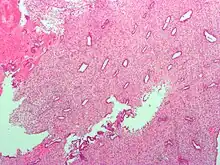

Endometrium in the proliferative phase

The endometrium consists of a single layer of columnar epithelium plus the stroma on which it rests. The stroma is a layer of connective tissue that varies in thickness according to hormonal influences. In the uterus, simple tubular glands reach from the endometrial surface through to the base of the stroma, which also carries a rich blood supply provided by the spiral arteries. In women of reproductive age, two layers of endometrium can be distinguished. These two layers occur only in the endometrium lining the cavity of the uterus, and not in the lining of the fallopian tubes where a potentially life-threatening ectopic pregnancy may occur nearby.[4][5]

• The functional layer is adjacent to the uterine cavity. This layer is built up after the end of menstruation during the first part of the previous menstrual cycle. Proliferation is induced by estrogen (follicular phase of menstrual cycle), and later changes in this layer are engendered by progesterone from the corpus luteum (luteal phase). It is adapted to provide an optimum environment for the implantation and growth of the embryo. This layer is completely shed during menstruation.

• The basal layer, adjacent to the myometrium and below the functional layer, is not shed at any time during the menstrual cycle. It contains stem cells that regenerate the functional layer,[1] which develops on top of it.